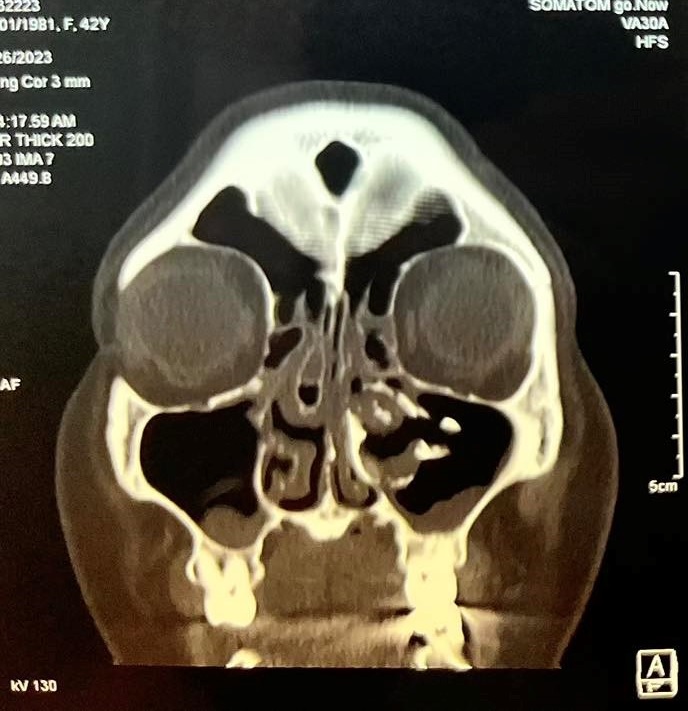

Gần đây bệnh nhân xuất hiện thêm đau nhức vùng mắt trái cùng bên nên đã đến khám tại Bệnh viện Quận 4. Qua nội soi thăm khám và thực hiện chụp CT-Scan phát hiện bệnh nhân có cấu trúc mật độ giống xương dính vào thành trong xoang hàm bên trái, đẩy lệch vách mũi xoang về phía vách ngăn gây hẹp hốc mũi bên trái kèm viêm xoang hàm sàng 2 bên và concha bullosa cuốn mũi giữa bên phải gây tắc nghẽn đường dẫn lưu của xoang hàm bên phải

Hình ảnh CT scans mũi xoang Đánh giá ca lâm sàng, Bác sĩ chuyên khoa II Đào Duy Tường – Trưởng khoa Tai Mũi Họng Bệnh viện Quận 4 nhận định : “ Đây là một trường hợp khá hiếm , tiến triển chậm, bệnh bắt đầu âm thầm ,ít triệu chứng cho đến khi các lỗ thông của xoang bị tắc nghẽn gây ra các triệu chứng đau nhức vùng mặt và khi khối u gây chèn ép hốc mũi bên trái gây cho bệnh nhân có cảm giác nghẹt mũi. Trong trường hợp này phẫu thuật tương đối khó khăn do hốc mũi hẹp, khó tiếp cận khối u , cần phải sử dụng những thiết bị và dụng cụ phẫu thuật chuyên biệt”